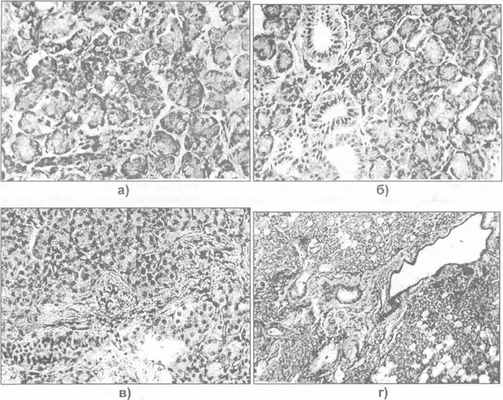

Рис. 23.1.2. Морфологическая структура околоушной железы: а) у ребенка; б) в юношеском возрасте; в) в среднем возрасте; г) пожилом возрасте ( имеется жировое перерождение и склероз паренхимы).

Основными структурными единицами паренхимы околоушной железы являются альвеолярные концевые секреторные отделы (ацинусы), компактно расположенные в дольках и состоящие из клеток железистого эпителия, между ними расположены мелкие протоки. Концевые секреторные отделы представлены пирамидальными цилиндрическими клетками, широким основанием которые прилежат к базальной мембране (рис. 23.1.2 - 23.1.3). Вблизи устья находятся бокаловидные клетки, выделяющие слизь, которые образуют химический барьер для восходящего проникновения микробов через протоки в железу. С возрастом увеличиваются зоны междольковой соединительной ткани, появляются участки жирового перерождения паренхимы с уменьшением массы концевых секреторных отделов и атрофией железистой ткани.